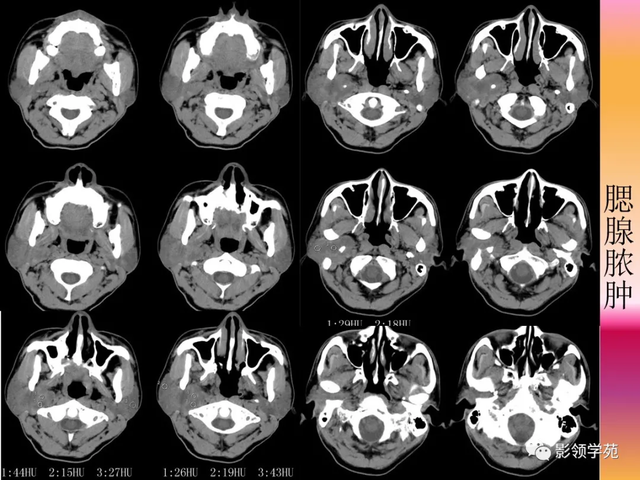

【影像体现】:右侧腮腺不规则增大,边缘强化不规则,CT值为15-44HU,内有低密度坏死区,且见脱离 ,周围显着 强化,未见肿大淋投合。

【影像诊断】:右腮腺脓肿。

2.腮腺脓肿:体现为腮腺局限性肿块并黑点状坏死,典型者可见环状强化,伴相近 筋膜增厚和皮下脂肪层模糊,团结 临床局部皮温升高可诊断。

病例3:男性,68岁,因“发现右耳垂下肿物30余年”:

病理:腺淋巴瘤

病例4:男性,81岁,因发现右耳下肿物10年余,举行 性增大2年: